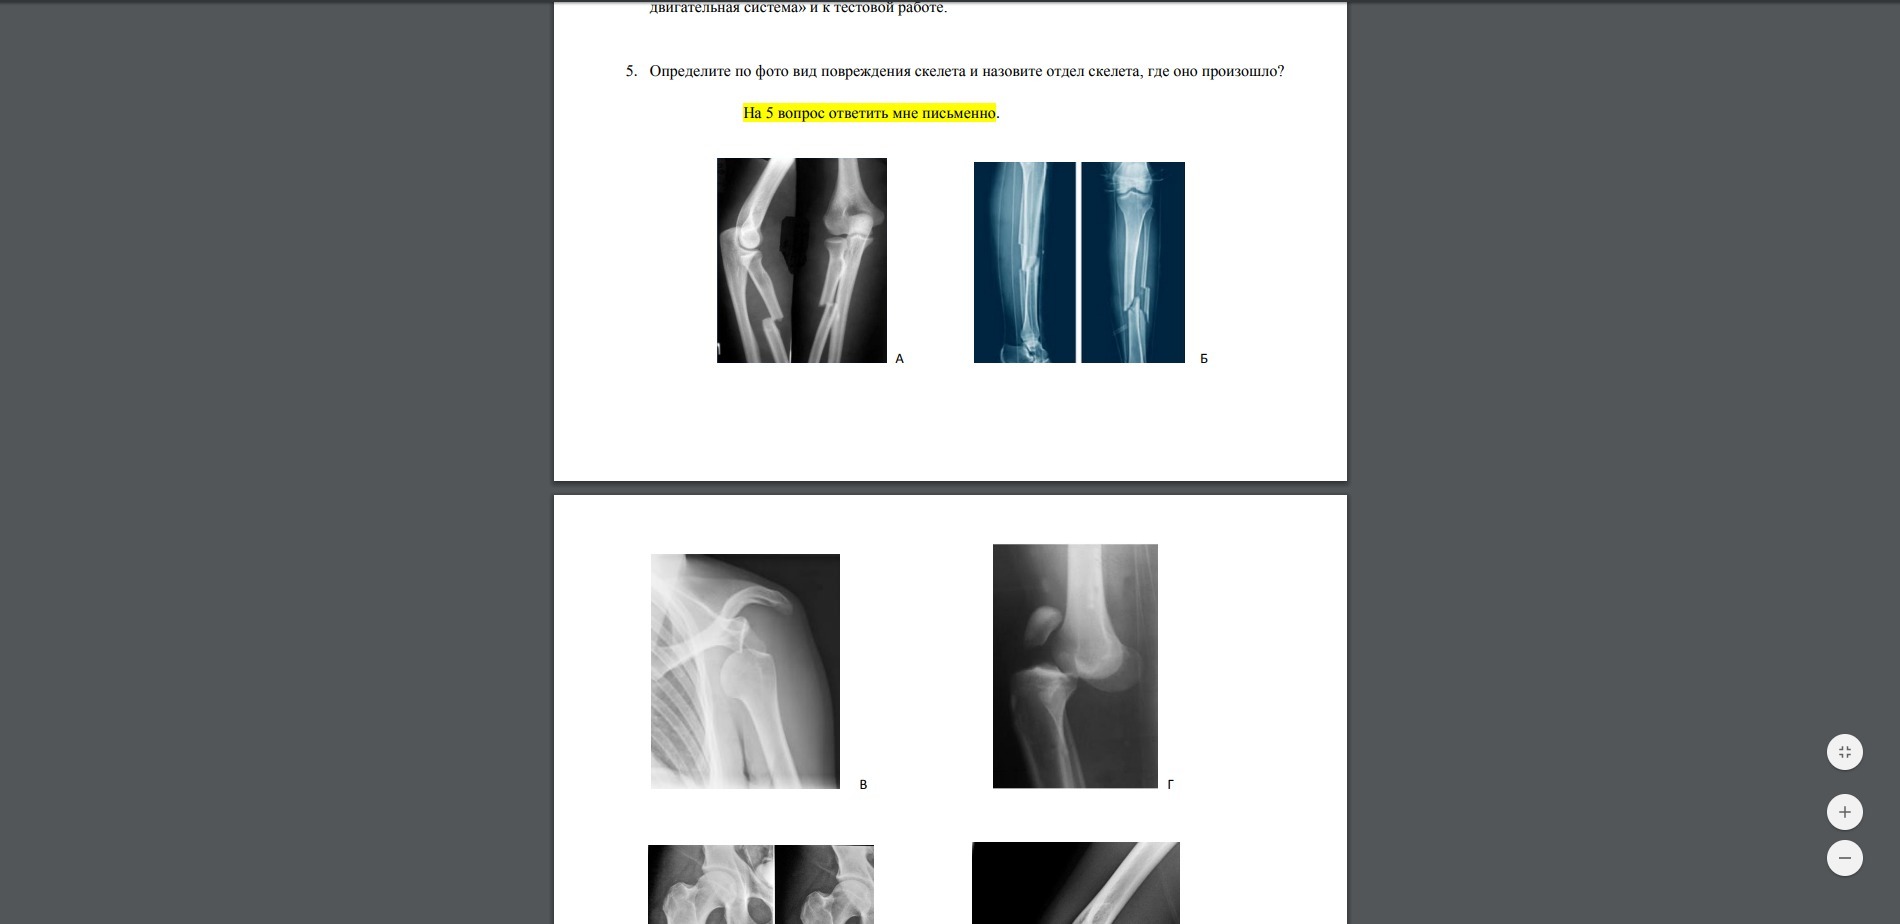

Ответы

первый перелом на колилини 2 перелом возле пятки 3 перелом на плече 4 перелом на колини